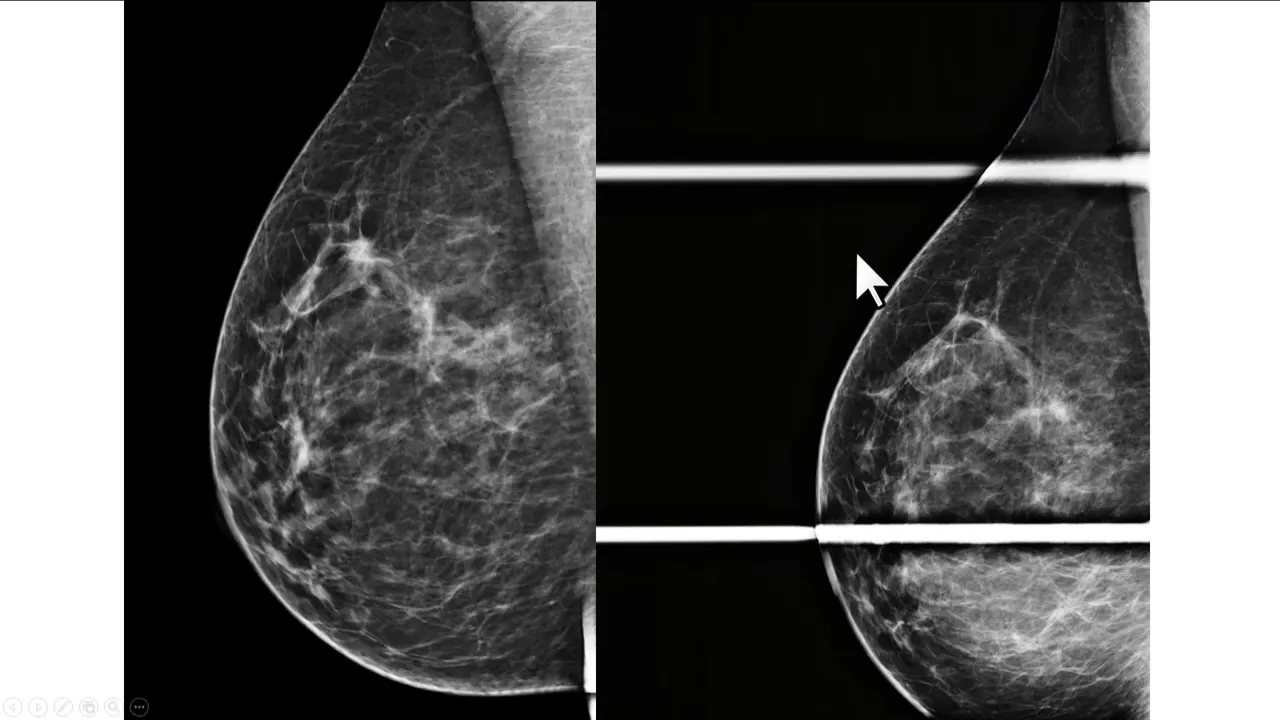

que nesses tema anterior a paciente tinha mais parei com a fibrilandular nos quadrantes superiores mas essa simetria que nos chamam atenção aqui na extremidade superior do Paraíso glandular não estava presente dessa forma precisamos realizar uma incidência monográfica complementar para nos certificar que esse achado e não tem importância Clínica a recomendação nesses casos é a compressão focal preferencialmente realizada na incidência em perfil veja que no perfil aparece menos um músculo peitoral maior do que aparece na incidência né de lateral oblíqua a compressão no perfil ajuda de associar a disposição do parenque os nódulos reais se Mantena

com pressão no perfil enquanto a sobreposição do parênquima é resolvida Principalmente quando a incidência do perfil é complementada com a compressão localizada veja que a maior parte da força do compressor foi aplicada na região de interesse passa a ser melhor avaliada depois da incidência complementar nós podemos interpretar esse achado como irrelevante ele pode ser descrito como uma sobreposição de parenquima justificando uma simetria nesse caso classificado na categoria B2 ou então nem precisa ser descrito mas o exame continuarei sendo classificada na categoria devido aos achados cicatriciais não é contra lateral se você ainda não está inscrito